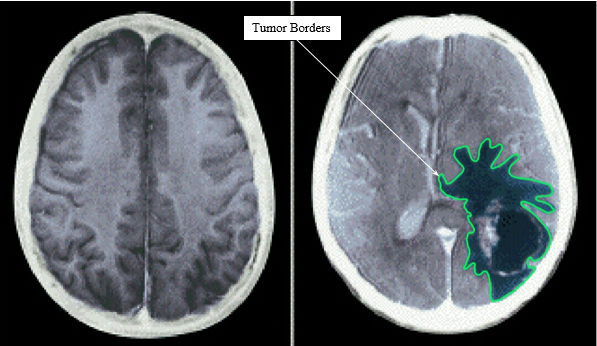

Figure 1 and Figure 2 are CT scan images of two malignant brain tumors. It can be inferred that while a benign tumor has an almost smooth round shape, malignancy can be identified by the existence of invading edges. Two major morphologies of the malignant brain tumors are identified by solid lines in Figure 1 and Figure 2. The first morphology resembles a polygonal shape while the second one resembles a star. In the present numerical analysis, the tumor malignancy was simulated in two different scenarios: